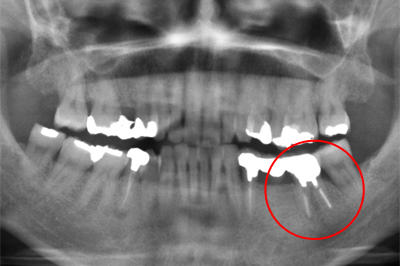

インプラント施術例

歯を削りたくない、入れ歯をどうしても入れたくないという時、インプラント治療を行っています。

施術前

施術後

レントゲン